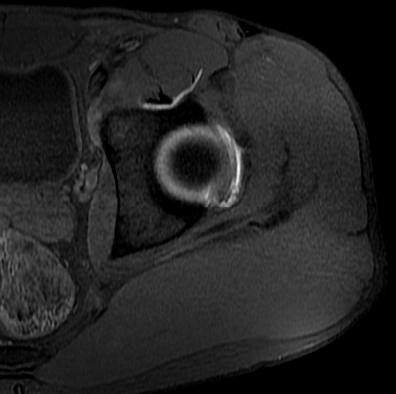

Hoại tử vô mạch chỏm xương đùi (Osteonecrosis of the femoral head)